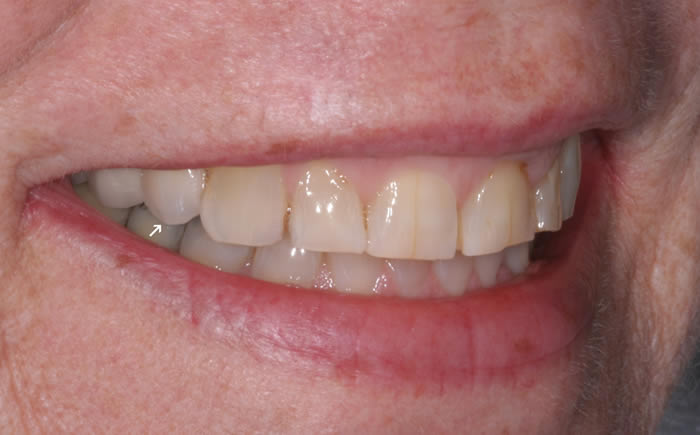

More back teeth replaced by dental implants

Case Three (2 images)

Case Four (4 images)

Case Five (4 images)

Case Six (8 images)

Case Seven (4 images)